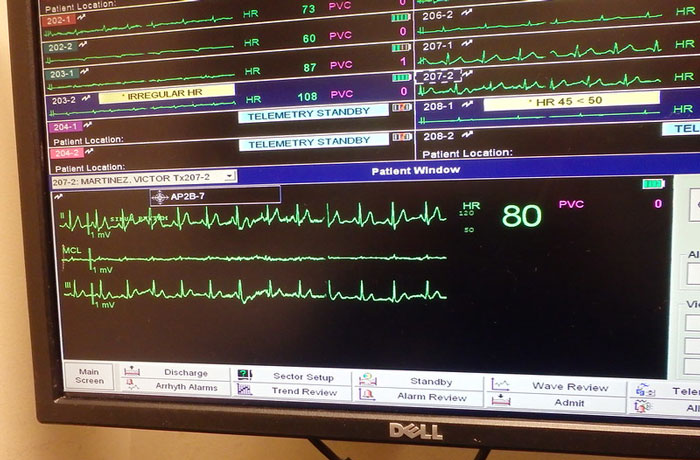

I have a rare heart disease, it’s called Wolff Parkinson white, and so when i am attached to a heart monitor my heart rate is different then everyone else - it beats weird

kodythehoedy , Eli Christman Report